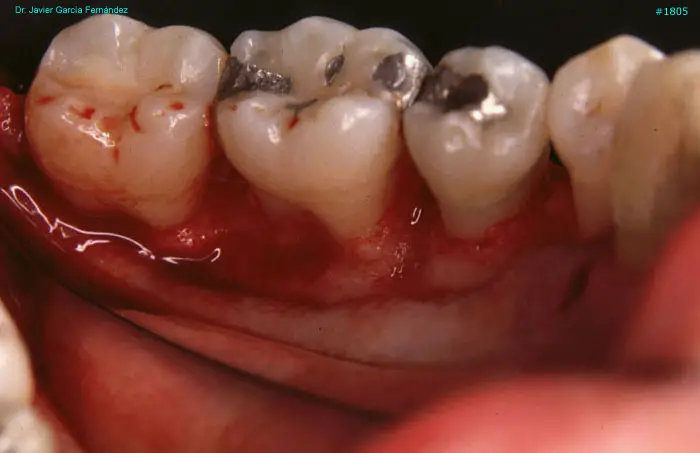

image 71